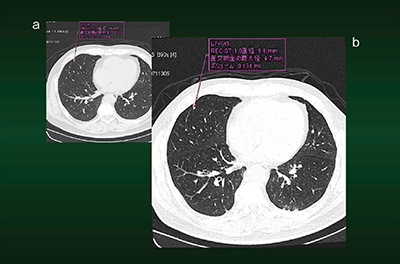

症例1は,52歳,女性。小さな結節性病変の経過観察中に,CTにてconsolidation(浸潤影)と思われる病変が認められた(図2 a)。この病変にマーキングをしておけば,フォローアップの際に同じ断面の画像が瞬時に画面上に並列表示されるため,比較が容易である。本症例では,6か月後の画像で病巣の消失が確認された(図2 b)。

図2 症例1:Lung CAREによる経時的画像比較